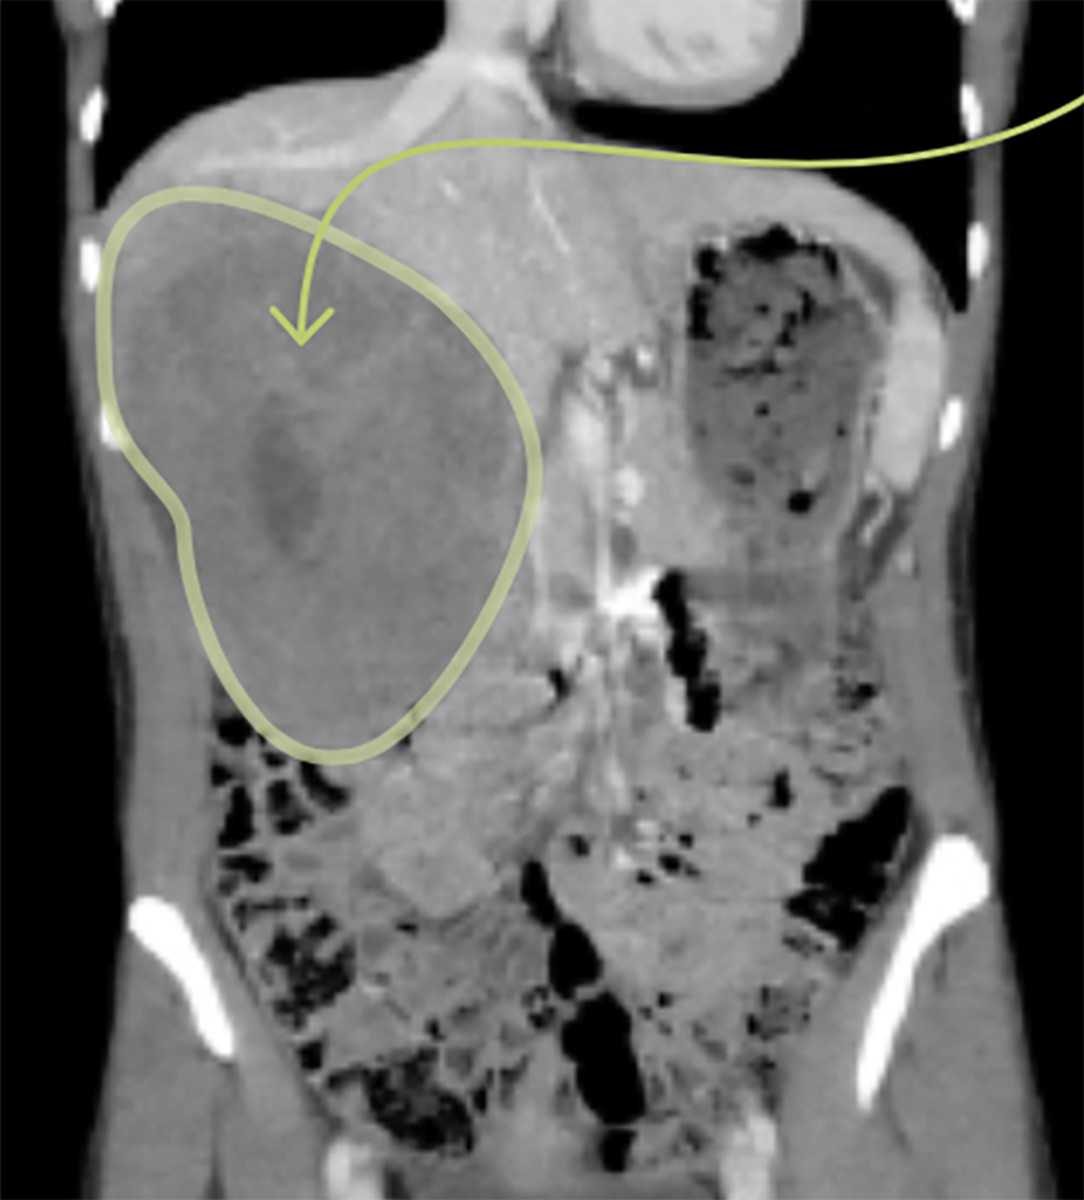

Then the ACC came back last summer in the form of a cantaloupe-sized tumor that absorbed two thirds of her liver. Doctors took it out, leaving a 13-inch, purple fishhook-shaped scar on Gabe's abdomen. Six months later, the ACC came back again, this time in the form of 12 small tumors on her liver. Multiple treatment options were considered, and rejected, before doctors prescribed a course of chemotherapy. Gabe delayed treatment to try to achieve the qualifying standard, 4:09.52, for last month's U.S. national championships—that would be her goal for the year. Her season’s training had started late because of the abdomen surgery, but she was in respectable shape. Now she would have to hurry to qualify before chemo. “We were going to have to cram a lot of training into a short time, which is never a good thing,” said Gabe’s longtime professional coach, Dennis Barker.

Doctors at first estimated the lesion to be roughly six by five inches and shaped like a rugby ball. Justin saw the scan. Gabe didn’t want to see it; she felt an immediate urge to vomit. “I had this alien inside of me,” she says, “and I kept telling Justin, ‘Get it out!’ At the same time, I knew it wasn’t coming out today or tomorrow.”

Medical uncertainty is a terrifying thing; Justin sought to accelerate the time line. He texted a fellow resident and asked for help in locating a liver specialist, and he was put in touch with Julie Thompson at M Health, who immediately fast-tracked Gabe’s case. “I just imagined how frightened they must be,” says Thompson, “how overwhelming it must have felt.” Thompson arranged to have Gabe’s CT scan shared with a group of 25 cancer doctors at their weekly “tumor conference” five days after Justin had hugged Gabe. “I pulled up Gabe’s images,” says Thompson, “and there was just this silence, then a sort of gasp, like Ahhh. It was such an impressive tumor in such a young, fit person.” The consensus at the conference: The tumor would almost certainly prove cancerous. A biopsy was performed the following week, and Gabe got the news in a text from Thompson while she was driving with Justin to his family’s vacation home on Pelican Lake, 200 miles north of Minneapolis. Her ACC had returned.

ACC most commonly metastasizes to the lungs, far less often in the liver. In other words, Gabe had a rare version of a rare cancer. There was some good news, though: The new tumor was resectionable, meaning that it could be removed, and with it, in theory, would come all the new cancer, still leaving enough of the liver that it would grow and return to full capacity. (Further recurrence of metastatic cancer was still likely.) On the morning of Aug. 26, Eric Jensen, a 44-year-old professor of surgical oncology at M Health, performed a five-hour, extended right hepatectomy on Gabe, removing the tumor along with her gall bladder (which, essentially, was in the way).

Jensen started with his scalpel. “It’s a tough incision,” he says. “The majority of liver surgery is done less invasively—laparoscopically or with a small incision—but this was a large tumor in a small-framed woman.” The incision went through every layer of Gabe’s abdominal wall. Jensen initially struggled to pull the tumor out from beneath Gabe’s rib cage; when he finally succeeded he instructed his scrub nurse to call Justin, who was out running because he dislikes hospital waiting rooms. “It sounded like they were having a party in the operating suite,” Justin remembers.

The tumor Jensen removed—the one that was growing in Gabe’s torso when she ran the Olympic Trials—was 6.3 inches long, six inches wide and almost four inches thick, bigger than believed. It weighed about four pounds, slightly less than a two-liter bottle of soda.